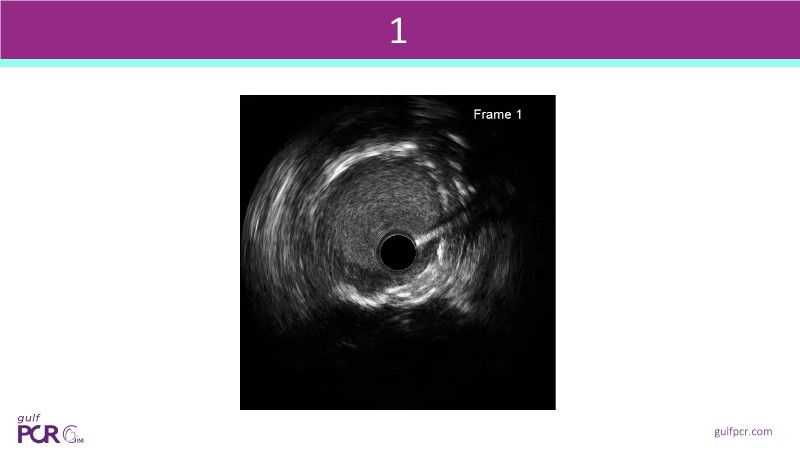

Calcified coronary lesions are a major challenge in PCI. This PCRGulf-GIM 2025 session showcases a complex case with intravascular imaging, highlighting how IVUS 123 guides each step.

From planning the procedure and understanding calcium distribution, to lesion preparation with modern modification tools, and post-PCI assessment to confirm stent expansion and detect complications, this session demonstrates practical, imaging-driven strategies.

- To review the principles of IVUS 123 guiding modern PCI